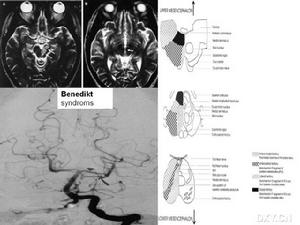

紅核綜合徵又稱Foix氏綜合徵。凡一側紅核病變引起同側動眼神經麻痹和對側上下肢運動障礙,儘管由病變範圍不同,可有不同的類型,統稱為紅核綜合徵。常見類型:Benedikt氏綜合徵,由Benedikt於1889年首先提出,大部分為血管性疾病引起,尤以梗塞多見。運動障礙不是錐體束性而為錐體外系性的,肌張力輕度增高,下肢伸肌較明顯,但非肌強直。未見痙攣性麻痹和病理征。此外有明顯的震顫或舞蹈樣運動等運動障礙。這種震顫可由隨意動作和特定姿勢使之增強,不規則,故與Parkinson氏綜合徵所見之靜止性震顫不同。

又稱中腦震顫綜合徵、紅核-眼綜合徵、紅核-脊髓小腦腳綜合徵...綜合徵、紅核震顫綜合徵、Souquez-Bertrand綜合徵。 【病...紅核與動眼神經、小腦結合臂。 【臨床表現】 病側動眼神經麻痹,可有復...